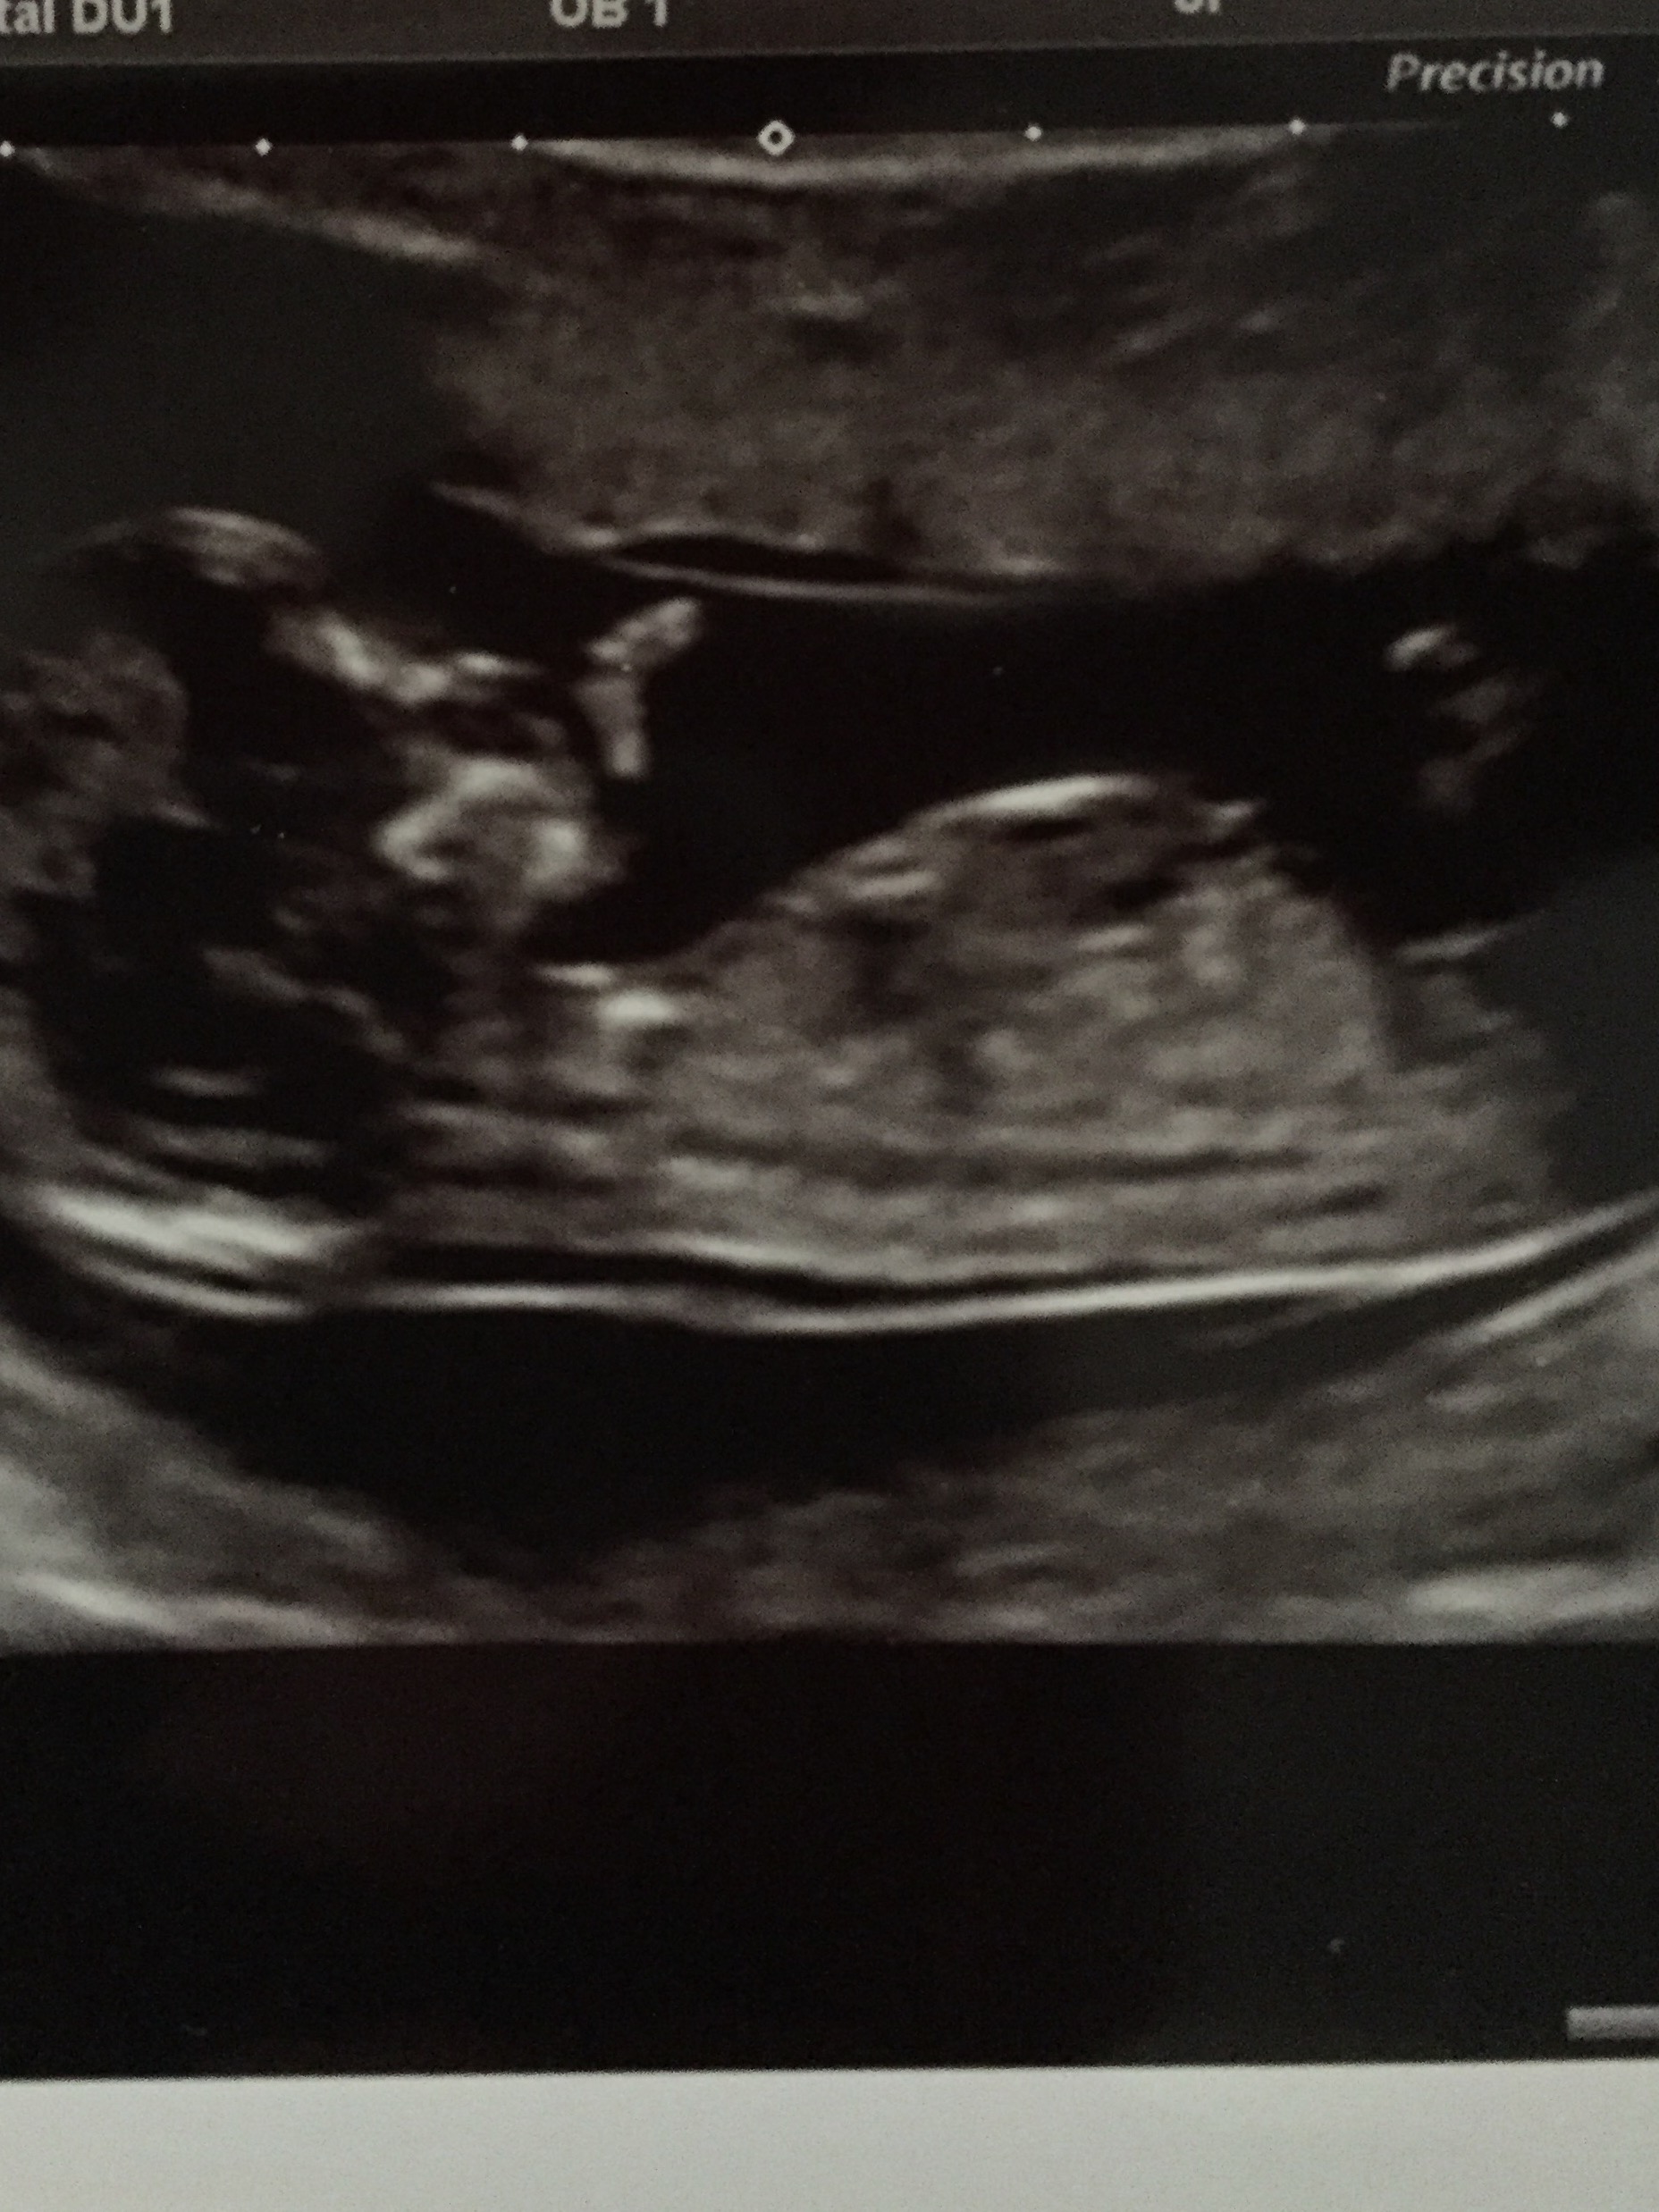

Any guesses would be greatly appreciated! Now 18+5 weeks! Desperate to find out!

The scan was at 13+1weeks X

If that's a nub I can see in the second pic then sorry to say but it looks like a boy to me. Hopefully I'm wrong!

First pic i thought girl. But second i think i see a boy nub.

I think girl. IMO at 13w+ the nub would be more angled if it was a boy.

Arrh that's why I am soo confused! The bottom photo has a possible nub lower down which looks very boy. However the top photo shows it clearly higher up but it's missing the end

Thought girl on first photo but in the second photo there seems to be a boy nub showing, so I'd guess boy on this one! xx